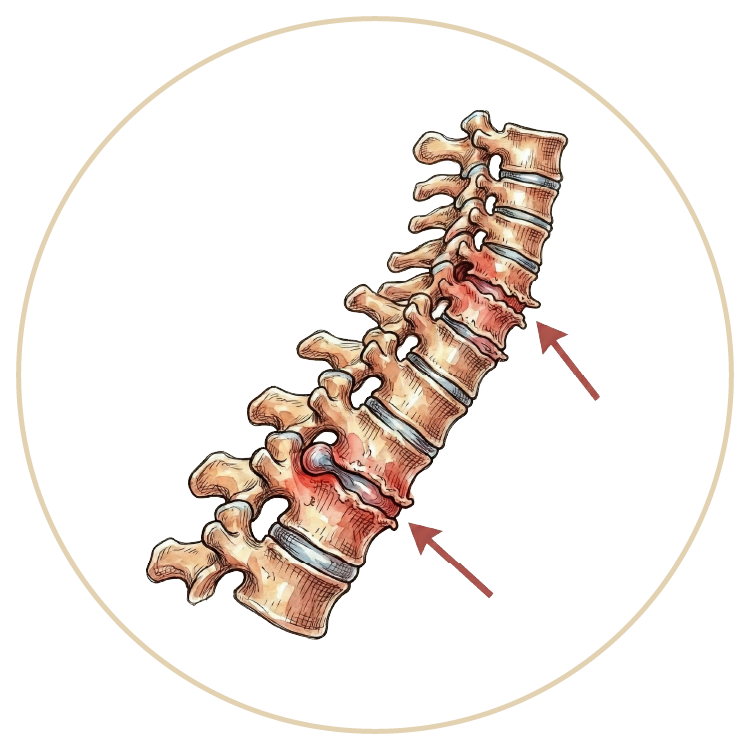

Omurga (Bel - Boyun - Sırt) Hastalıkları

OmurgaHastalıkları

Skolyoz